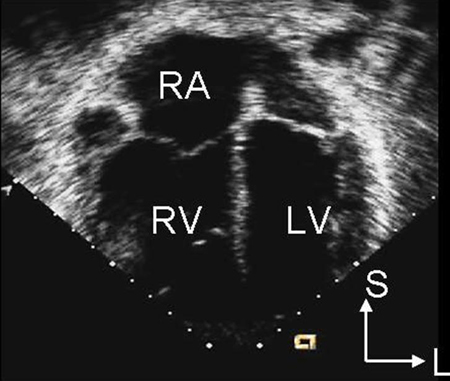

CXR is not helpful in determining the subtype and may be normal with a small ASD. ECG may also be normal in small secundum, sinus venous, and unroofed coronary sinus ASDs. With a larger shunt, there may be right atrial enlargement, right ventricular hypertrophy, or right axis deviation.[Figure caption and citation for the preceding image starts]: Parasternal short axis echocardiographic image demonstrating right ventricular enlargement in a patient with an ASD. (RV) right ventricle; (LV) left ventricleImage courtesy of Patrick W. O'Leary, MD [Citation ends].

[Figure caption and citation for the preceding image starts]: Apical 4-chamber echocardiographic image demonstrating right ventricular enlargement in a patient with an ASD. (RA) right atrium; (RV) right ventricle; (LV) left ventricleImage courtesy of Patrick W. O'Leary, MD [Citation ends].